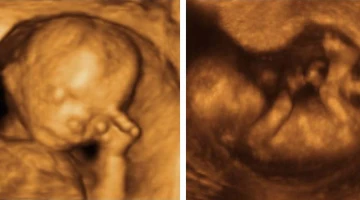

Médico conmueve a padres invidentes con ecografía de su bebé en alto relieve

Melisa muestra la ecografu00eda en alto relieve de su hijo. Cru00e9dito: Noticias Caracol (captura de video)

Por Eduardo Berdejo

Melisa y Jaime son dos padres invidentes que quedaron conmovidos cuando su médico, Jezid Miranda, les entregó uno de los... Leer más